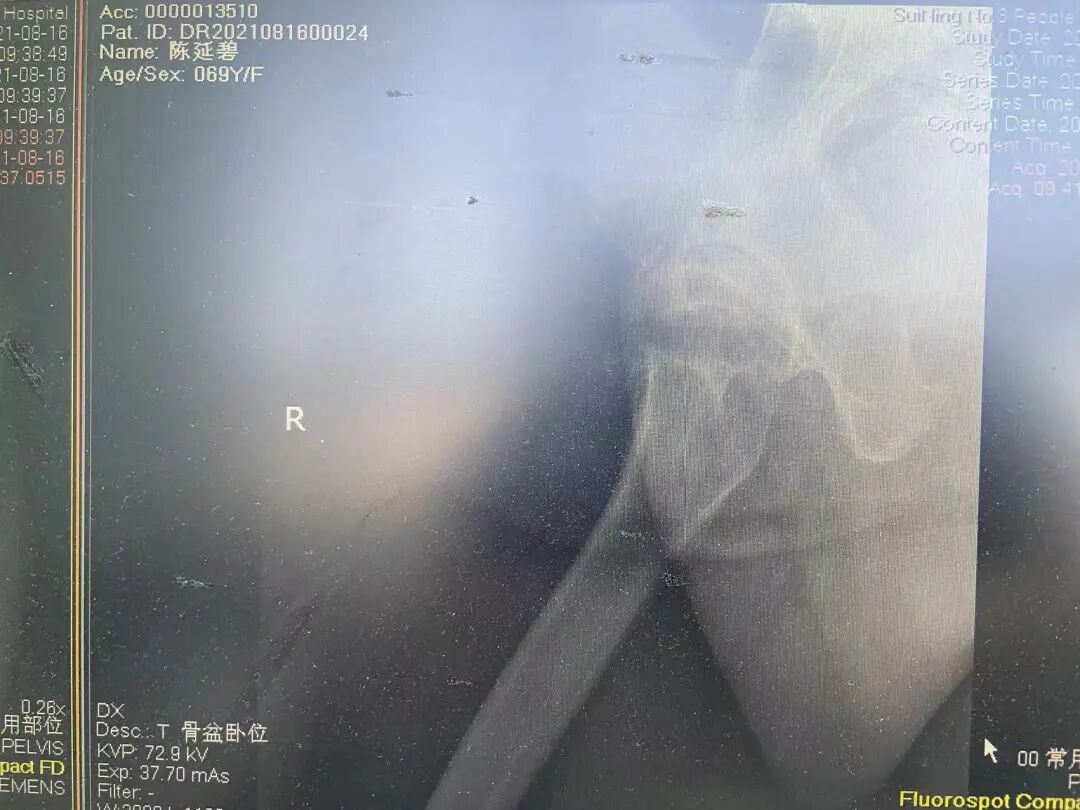

老年左侧股骨颈骨折

人工股骨头置换术